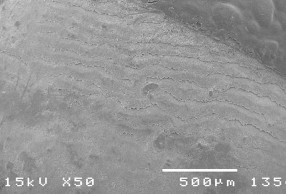

Hình ảnh tổn thương bề mặt dưới SEM.

Hình 3.4: Bề mặt răng bình thường ở độ phóng đại 50 – 3500 lần.

Hình 3.5: Bề mặt răng tương ứng sâu răng D1 ở độ phóng đại 50 – 3500 lần.

Hình 3.6: Bề mặt răng tương ứng sâu răng D2 ở độ phóng đại 500 – 2000 lần.